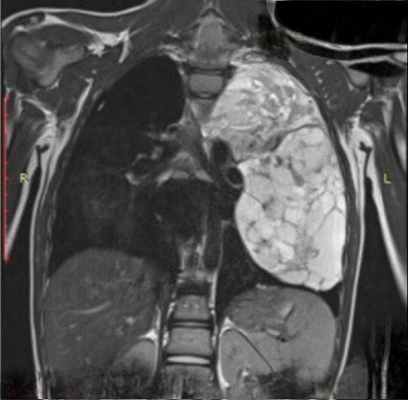

Там, где есть возможность выполнения МРТ, периодически возникает спор о том, что лучше, что хуже. На сегодняшний день нет какого-то единого однозначного мнения о том, как и когда нужно применять МРТ при патологии средостений.

Мы знаем сегодня, что возможность спиральной многосрезовой компьютерной томографии (МСКТ) (особенно, когда она выполняется с внутривенным контрастированием) и МРТ равны при некоторых минимальных преимуществах того и другого метода.

Учитывая, что КТ более распространено, более доступно в большинстве лечебных учреждений, на сегодняшний день она является первоочередным методом. Когда имеет смысл выполнять МРТ. Когда речь идет о патологии сердца и крупных сосудов средостения. Особенно у пациентов, у которых имеется реакция на рентгеноконтрастные препараты (их невозможно вводить или это опасно для пациента).

Когда речь идет о патологии паравертебральной области (нейрогенные опухоли или дифференциальная диагностика таких образований с патологией позвоночника. Натечник при туберкулезных спондилитах, лимфостатические поражения позвонков. Подозрения на кистозное образование. МРТ, как и УЗИ, гораздо лучше позволяет дифференцировать жидкостные образования от тканевых.

Рецидивы злокачественных опухолей – еще одно показание к магнитному резонансу. Это лимфомы, рецидивы рака легкого, когда использование этой технологии вместе с внутривенным контрастированием иногда помогает поставить правильный диагноз.

Один из типичных примеров. Преобразование кистозного образования энтерогенной кисты средостения при различных последовательностях МРТ делает совершенно понятным диагноз, что может вызывать затруднение при компьютерной томографии.